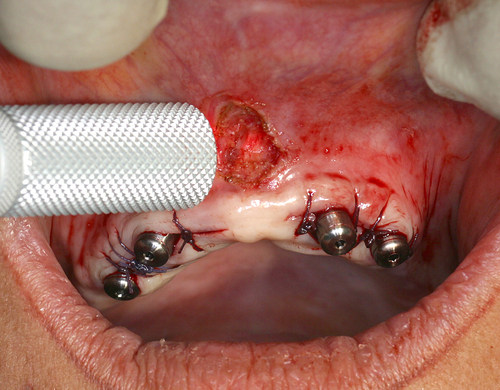

Une biostimulation postopératoire est faite avec un rayonnement pénétrant afin d’obtenir une cicatrisation très rapide (fig.24).

Fig. 24

Biostimulation postopératoire